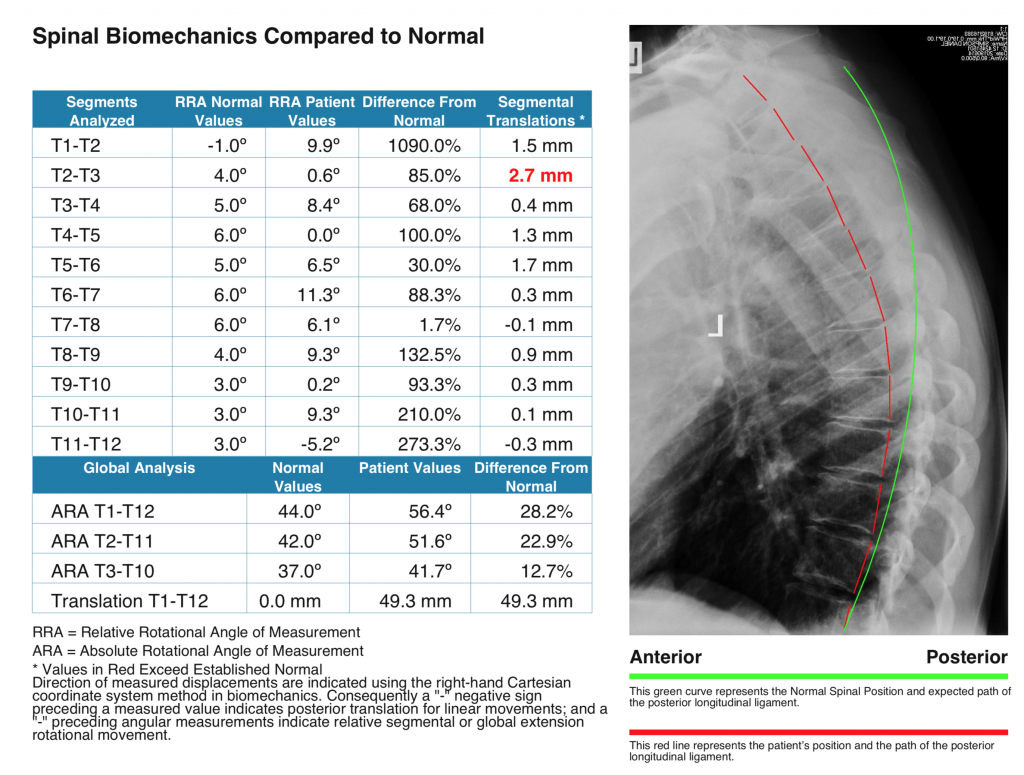

Digital X Ray Analysis Results You Can Take Home